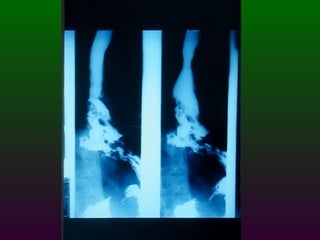

SEGD PATOLOGÍA ESOFÁGICA AFECCIONES DIVERSAS: Hernia de Hiato Divertículos Desgarro de Mallory Weiss y rotura esofágica

SEGD PATOLOGÍA ESOFÁGICAAFECCIONES DIVERSAS: Hernia de Hiato Divertículos Desgarro de Mallory Weiss y rotura esofágica